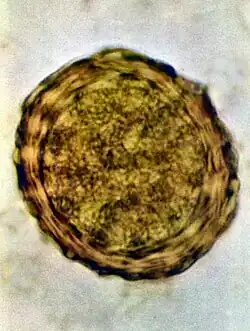

Os ovos tem a princípio cor branca, mas devido ao contato com os pigmentos biliares das fezes, adquirem um tom castanho, às vezes descrito como de amarelo-escuro a marrom.[9] Tem formato oval a redondo e medem 45 a 75 micrômetros (μm) de comprimento e 35 a 45 (ou 50, a depender da fonte)[10] μm de largura;[11] possuem uma cápsula espessa graças a membrana externa mamilonada, formada por mucopolissacarídeos e secretada pela parede uterina. Internamente a esta membrana, existe outra constituída de quitina e proteína. A mais interna é delgada e impermeável à água constituída de 25% de proteínas e 75% de lipídios. É a camada mais interna que garante ao ovo a capacidade de resistir às condições adversas do ambiente. Em seu interior, os ovos tem uma massa de células germinativas. É possível encontrar nas fezes humanas ovos inférteis de áscaris, isso ocorre quando a fêmea do verme não foi inseminada, ou quando está iniciando a oviposição.[10] Pode-se identificar ao microscópio esse tipo de ovo pois eles possuem o interior desorganizado, com citoplasma granuloso e sem estruturas visíveis.[9][11] A membrana mamilonada é mais delgada e são mais alongados que os ovos férteis, medindo 80 a 90 μm de comprimento. Algumas vezes, mesmo os ovos férteis podem não ter a membrana mamilonada, sendo chamados de ovos decorticados.[9]